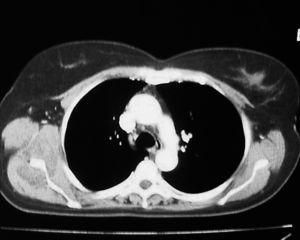

Mujer de 40 años, fumadora, que consultó por un bulto no doloroso en región escapular de un año de evolución que aumentaba de tamaño, alcanzando 7 cm de diámetro. La RMN mostró una tumoración en músculo serrato mayor derecho, en contacto con la pared costal debajo del músculo dorsal ancho que se continúa hasta el músculo subescapular (fig. 1). Era compatible con tumor de alta agresividad, descartandose fibrohistiocitoma u otro sarcoma de partes blandas. Se realizó una biopsia incisional, en anatomía patológica con el resultado de ED. Se practicó una resección marginal, encontrando el tumor ampliamente adherido a la pared torácica y escápula. Se confirmó el diagnóstico de ED tras el análisis de la pieza.

Figura 1. Corte coronal de resonancia magnética nuclear (RMN) en el que se observa un elastofibroma dorsi; se aprecia la tumoración en contacto con la pared torácica bajo el músculo dorsal ancho.